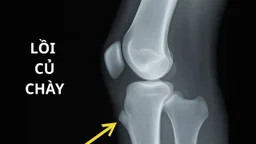

Để xác định nguyên nhân gây đau vùng đáy xương ngồi, bác sĩ sẽ thực hiện khám lâm sàng, kiểm tra khả năng vận động, mức độ đau và điểm đau khu trú. Các chẩn đoán hình ảnh được chỉ định như X-quang, MRI hoặc siêu âm giúp đánh giá chính xác tình trạng gân, xương và túi hoạt dịch. Trong đó, MRI đặc biệt hữu ích trong việc phát hiện viêm, rách gân hoặc chấn thương phần mềm quanh ụ ngồi.